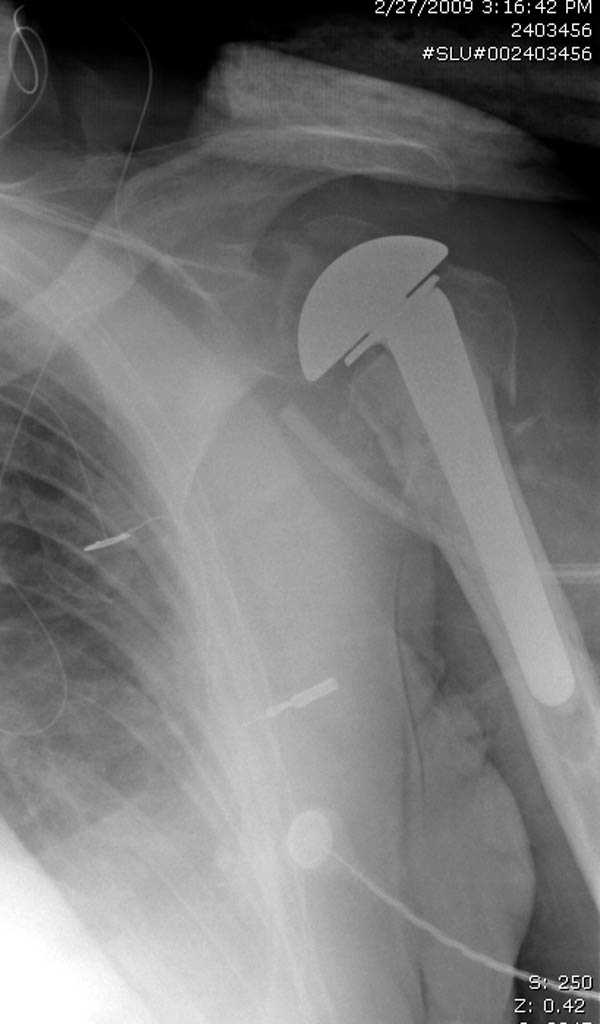

дополнительные снимки по протезированию

Djoldas Kuldjanov, MD

Department of Orthopedic Surgery

St. Louis University Medical Center